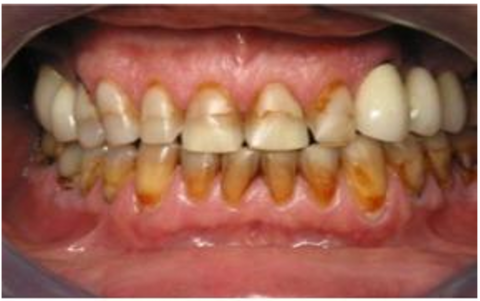

The dataset used in this study consists of 10,573 clinically sourced dental images, including contributions from publicly available repositories such as Kaggle. It provides a comprehensive foundation for training, validating, and testing the dental disease detection system [15]. The images are categorized into five distinct dental conditions: caries (2,382 images), gingivitis (2,349 images), hypodontia (1,251 images), mouth ulcers (2,541 images), and tooth discoloration (2,050 images) (Figure 1).

a

b

c

d

e

Figure 1. Dataset samples. (a) Caries, (b) Gingivitis, (c) Hypodontia, (d) Mouth ulcers, (e) Tooth discoloration